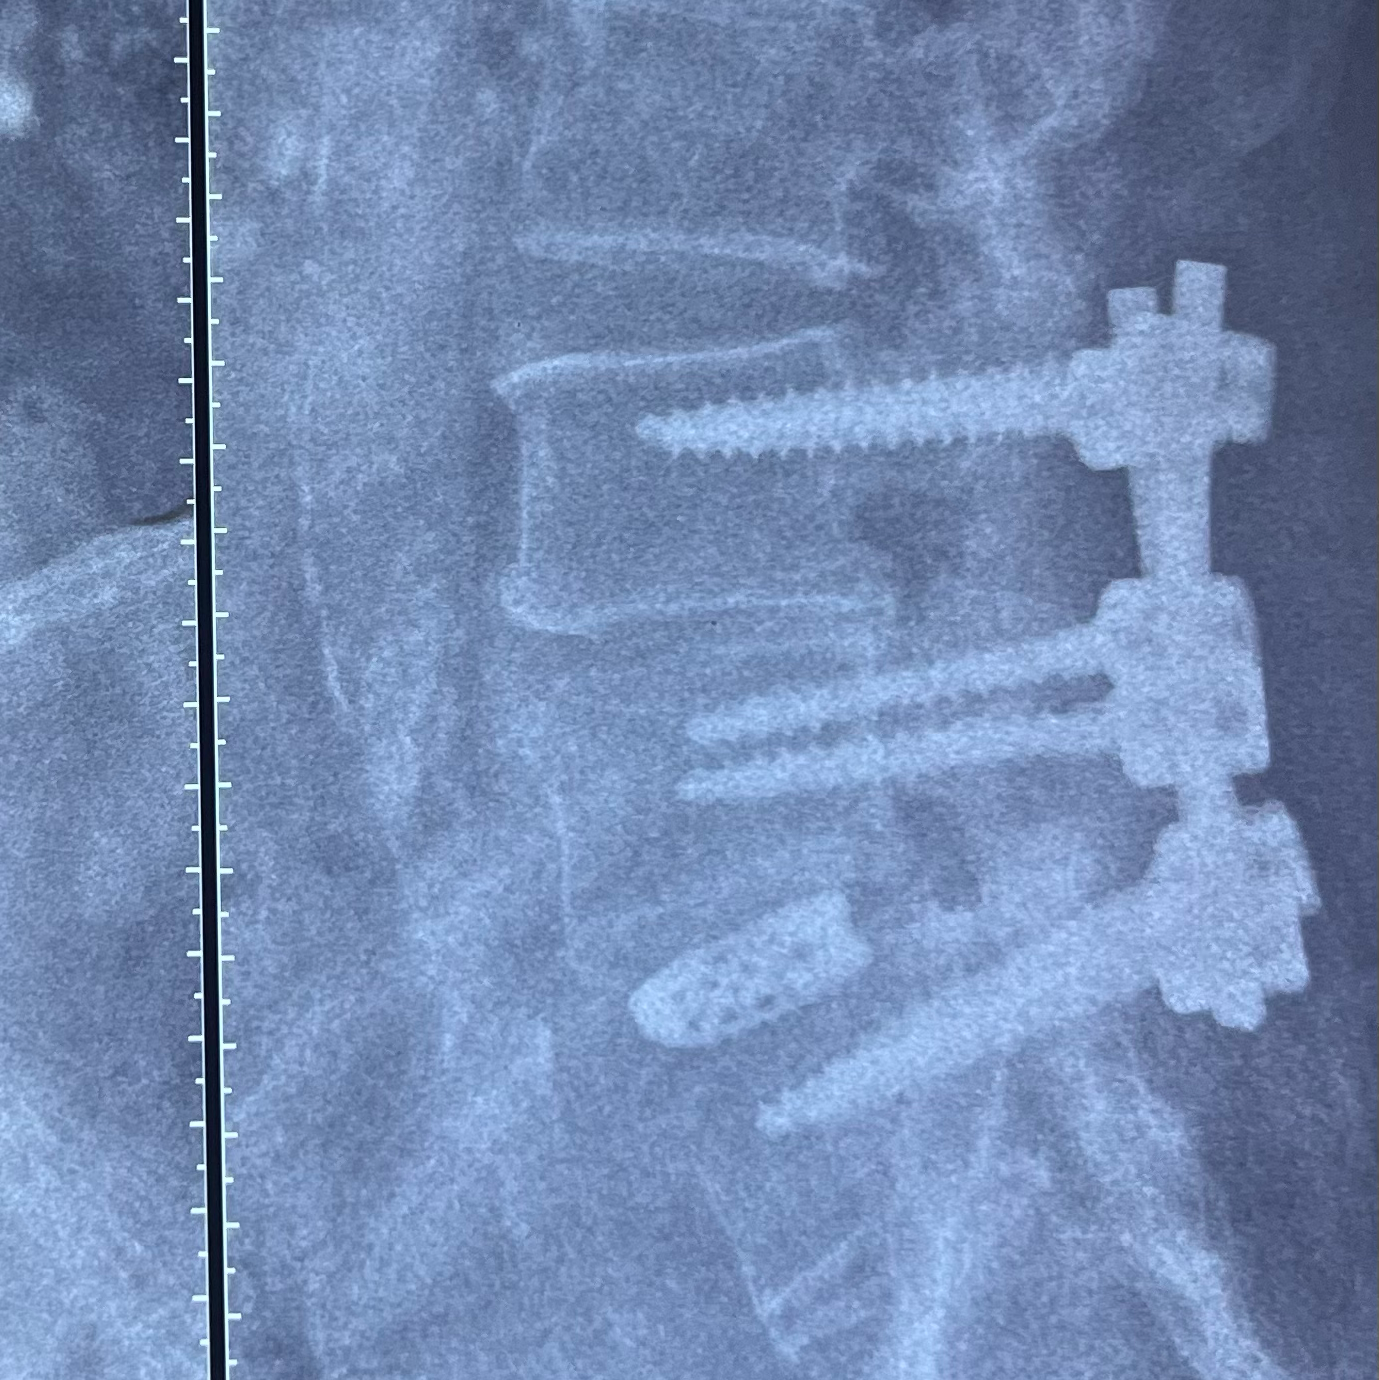

Understanding Tandem Stenosis and Its Successful Management Tandem stenosis refers to spinal canal narrowing at more than one level, most commonly affecting both the cervical and lumbar spine. In some cases, the thoracic (dorsal) spine may also be involved. This condition can lead to a combination of symptoms such as pain, numbness, weakness, and difficulty in walking due to multi-level nerve compression. Case Example: A 65-year-old female presented with lower back pain radiating to both legs, reduced walking and standing tolerance, and significant imbalance while walking. She required support and was unable to walk straight. She also experienced tingling, numbness, and heaviness in her legs, especially during prolonged standing or walking. Her MRI showed L5 spondylolisthesis with severe stenosis and nerve compression. Additionally, she had cervical myelopathy caused by disc herniation and osteophyte formation at the C5–C6 level. After detailed evaluation and counseling, she underwent simultaneous cervical and lumbar spine surgery under a single anesthesia session performed by Dr. Pramod Saini at Max Super Speciality Hospital. • Cervical Procedure: Anterior cervical corpectomy with cage and plate fixation • Lumbar Procedure: Pedicle screw fixation with laminectomy and decompression Outcome: The patient was mobilized within 2 days and discharged after 3 days. At 6-week follow-up, she showed significant improvement and was able to walk independently. This case highlights how modern surgical techniques allow safe and effective simultaneous management of tandem stenosis, reducing recovery time and improving patient outcomes.